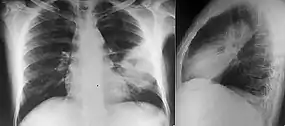

Various imaging modalities can also help with the diagnosis of melioidosis. In acute melioidosis with the spreading of the bacteria through the bloodstream, the chest X-ray shows multifocal nodular lesions. It may also show merging nodules or cavitations. For those with acute melioidosis without the spread to the bloodstream, chest x-ray most commonly shows upper lobe consolidation or cavitations.[8] In chronic melioidosis, the slowly progressing of upper lobe consolidation of the lungs resembles tuberculosis.[8] For abscesses located in other parts of the body apart from the lungs, especially in the liver and spleen, CT scan has higher sensitivity when compared with an ultrasound scan. In liver and splenic abscesses, an ultrasound scan shows "target-like" lesions while CT scan shows "honeycomb sign" (abscess with loculations separated by thin septa) in liver abscesses.[8] For melioidosis involving the brain, MRI have higher sensitivity than a CT scan in diagnosing the lesion. MRI shows ring-enhancing lesions for brain melioidosis.[8]